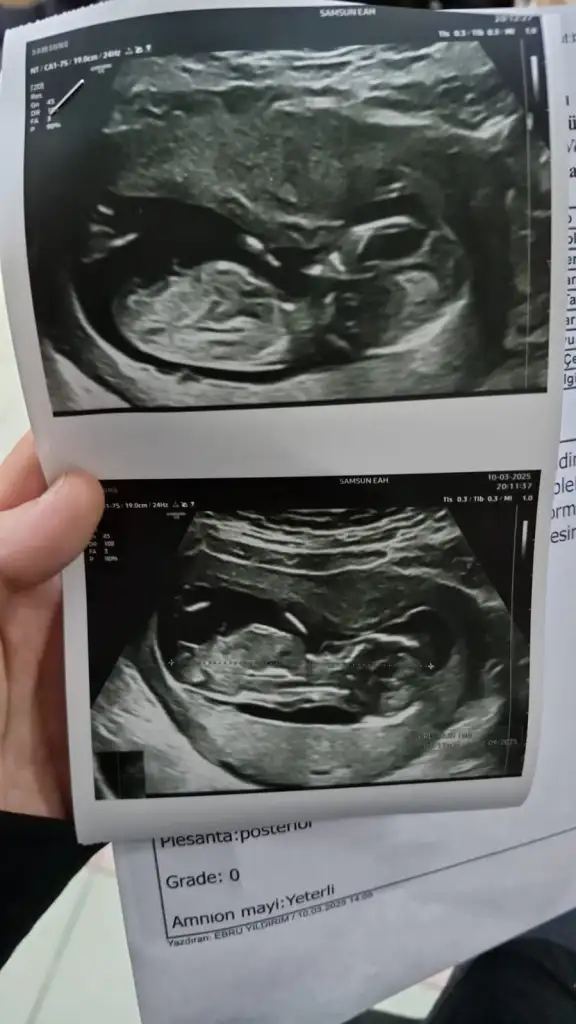

Kız2 Li taramadan ultrason goruntum cinsiyet tahmini yapabilecek olan var mıEki Görüntüle 3575149

Öğrendiniz mi bilmiyorum ama sizinki erkeğe çok benziyor13 hafta bize de bakar mısınız?

Benimkine de bakarmısnız 8 hafta 6 günlük karımdan ulturason görüntüsüVajinal bakıldı demişsiniz, kız olabileceğini düşünüyorum Ramzi teorisine göre.

Çok küçük daha tabi 7-8 haftalık olsa daha iyi anlaşılırdı

Benimde ultrason fotoğrafinda keseye bakıp tahmin edebilirmsnzGörüntü çok net değil ama erkek olabilir